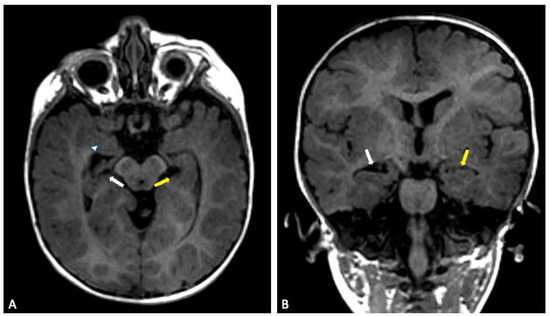

Background/Objectives: PPP2R1A encodes the scaffold subunit Aα of protein phosphatase 2A (PP2A). Pathogenic variants cause Houge-Janssens syndrome 2, a rare neurodevelopmental disorder characterized by developmental delay, intellectual disability, epilepsy, and brain malformations. We systematically reviewed published cases to define the clinical spectrum, [...] Read more.

Background/Objectives: PPP2R1A encodes the scaffold subunit Aα of protein phosphatase 2A (PP2A). Pathogenic variants cause Houge-Janssens syndrome 2, a rare neurodevelopmental disorder characterized by developmental delay, intellectual disability, epilepsy, and brain malformations. We systematically reviewed published cases to define the clinical spectrum, characterize the mutational landscape, and explore genotype–phenotype correlations. Methods: We conducted systematic searches of PubMed, Embase, and Web of Science from inception to March 2025, supplemented by GeneReviews and OMIM references. Studies reporting PPP2R1A variants with clinical data were included. Data extraction followed PRISMA guidelines, encompassing study characteristics, genetic findings, and phenotypic features. Results: We identified 16 studies representing 60 patients with PPP2R1A-related disorders. Twenty-six distinct pathogenic variants were identified; these were predominantly de novo heterozygous missense changes clustering within HEAT repeats 5–7. Recurrent hotspots included p.Arg182Trp (n = 12) and p.Arg183Gln (n = 5). Developmental delay and intellectual disability were universally present in all patients for whom data were available (100%, 58/58). Epilepsy occurred in 50.9% (29/57), and structural brain abnormalities in 83.1% (49/59), with corpus callosum abnormalities (40.7%, 24/59) and ventriculomegaly (32.2%, 19/59) being most frequent. Microcephaly was reported in 17.2% (10/58) and macrocephaly in 25.9% (15/58), while dysmorphic features were present in 53.4% (31/58). The phenotypic spectrum ranged from severe neonatal presentations with high mortality to milder neurodevelopmental courses, with prenatal manifestations including ventriculomegaly, corpus callosum abnormalities, and rare cardiac defects. Clear genotype–phenotype correlations emerged, with HEAT5 variants (p.Arg182Trp, p.Arg183Gln) associated with severe phenotypes and increased mortality, while p.Arg258His variants demonstrated comparatively milder courses. Conclusions: PPP2R1A-related disorders encompass a broad clinical spectrum ranging from lethal neonatal disease to survivable forms with variable neurodevelopmental outcomes. Prenatal features including ventriculomegaly and corpus callosum abnormalities enable early genetic diagnosis, informing reproductive counseling. Recognition of recurrent hotspot variants and their phenotype associations facilitates diagnosis, prognosis, and genetic counseling. These findings provide evidence-based guidance for clinical management and highlight the importance of variant-specific prognostication in this emerging neurodevelopmental disorder. Full article

Show Figures

Figure 1